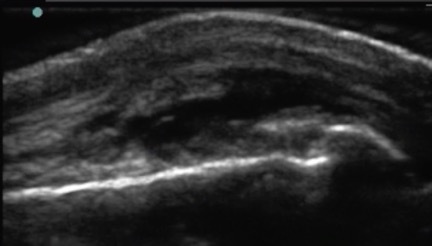

Hand MCP Joint Complex Synovial Fluid Image